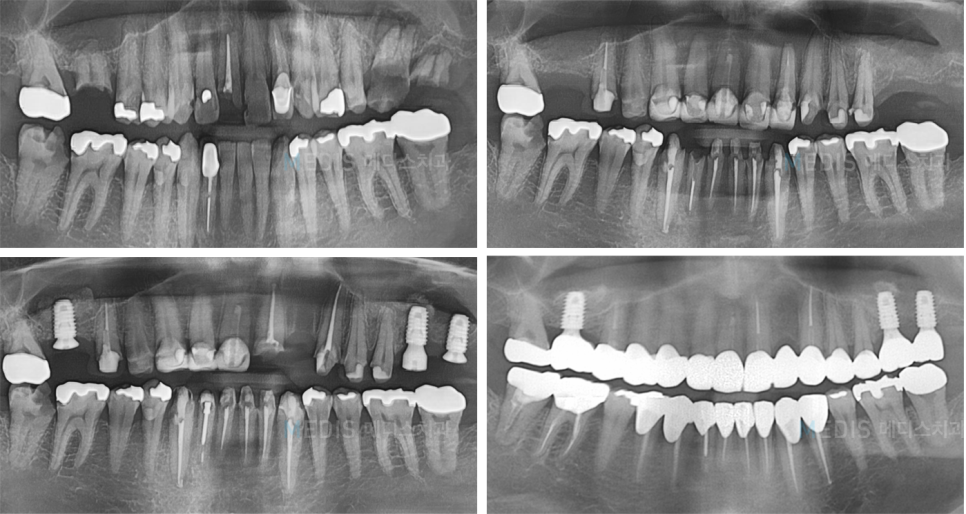

[디지털보철] 심한 치아우식 일반치료 및 임플란트 치료 후기

충치치료 + 임플란트 치료 전

※ 치료기간 : 2018.06.23~2018.12.22

(치료기간은 환자분의 협조도에 따라 달라질 수 있습니다)

※ 부작용 : 환자의 경향에 따라 통증, 부종과 멍 등의 부작용이 생길 수 있습니다.

* 상기 사진은 본원에서 치료를 받은 분의 동의를 얻은 사진으로 실제와 차이가 있을 수 있습니다.